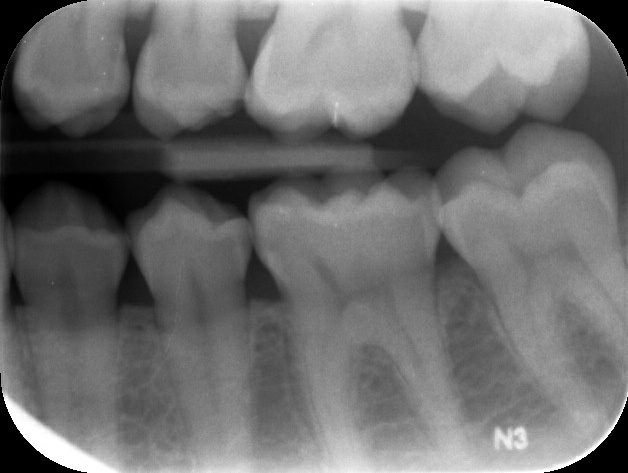

Ik ben vandaag bij een nieuwe tandarts geweest ivm verhuizing. Deze heeft geconstateerd dat mijn tandglazuur vrijwel verdwenen is, want dat is onder meer te zien aan de witte vlekjes aan de onderkant van mijn kiezen en daarnaast heb ik enkele gaatjes in mijn kiezen zowel rechts als links en boven en onder. Ik moet hem maar op zijn woord geloven, maar als ik deze foto's zie...dan zie ik geen gaatjes. Althans, ik ben geen tandarts hoor maar aan gaatjes dan zie je toch iets van een zwarte vlek of andere oneffenheden? De behandeling die hij voorstelde is: V92-A10 / V92-A10 / V92-A10 / V91-A10 / V91 / V92. Kostenplaatje zo'n 375 EU. Dit is een hoop geld en wil zeker weten of hij het bij het rechte eind heeft alvorens ik akkoord geef. Klopt het de begroting die hij voorstelde? Alvast bedankt!

Ik zie 6 gaatjes in 5 kiezen.

35 - 15 - 14 - 45 - 44 - 16